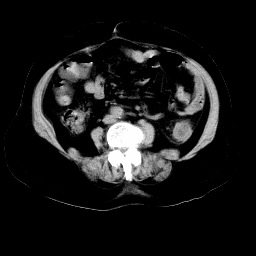

以下是引用arven在2008-11-9 10:13:00的发言:[br]肠壁增厚,形态较规则,支持降结肠炎症改变

以下是引用余辉在2008-11-9 9:47:00的发言:[br]各层面均可见降结肠管壁增厚,管腔狭窄,中部层面可见管壁明显增厚区,结合病史多考虑降结肠癌,溃疡性结肠炎不除外,建议进一步检查